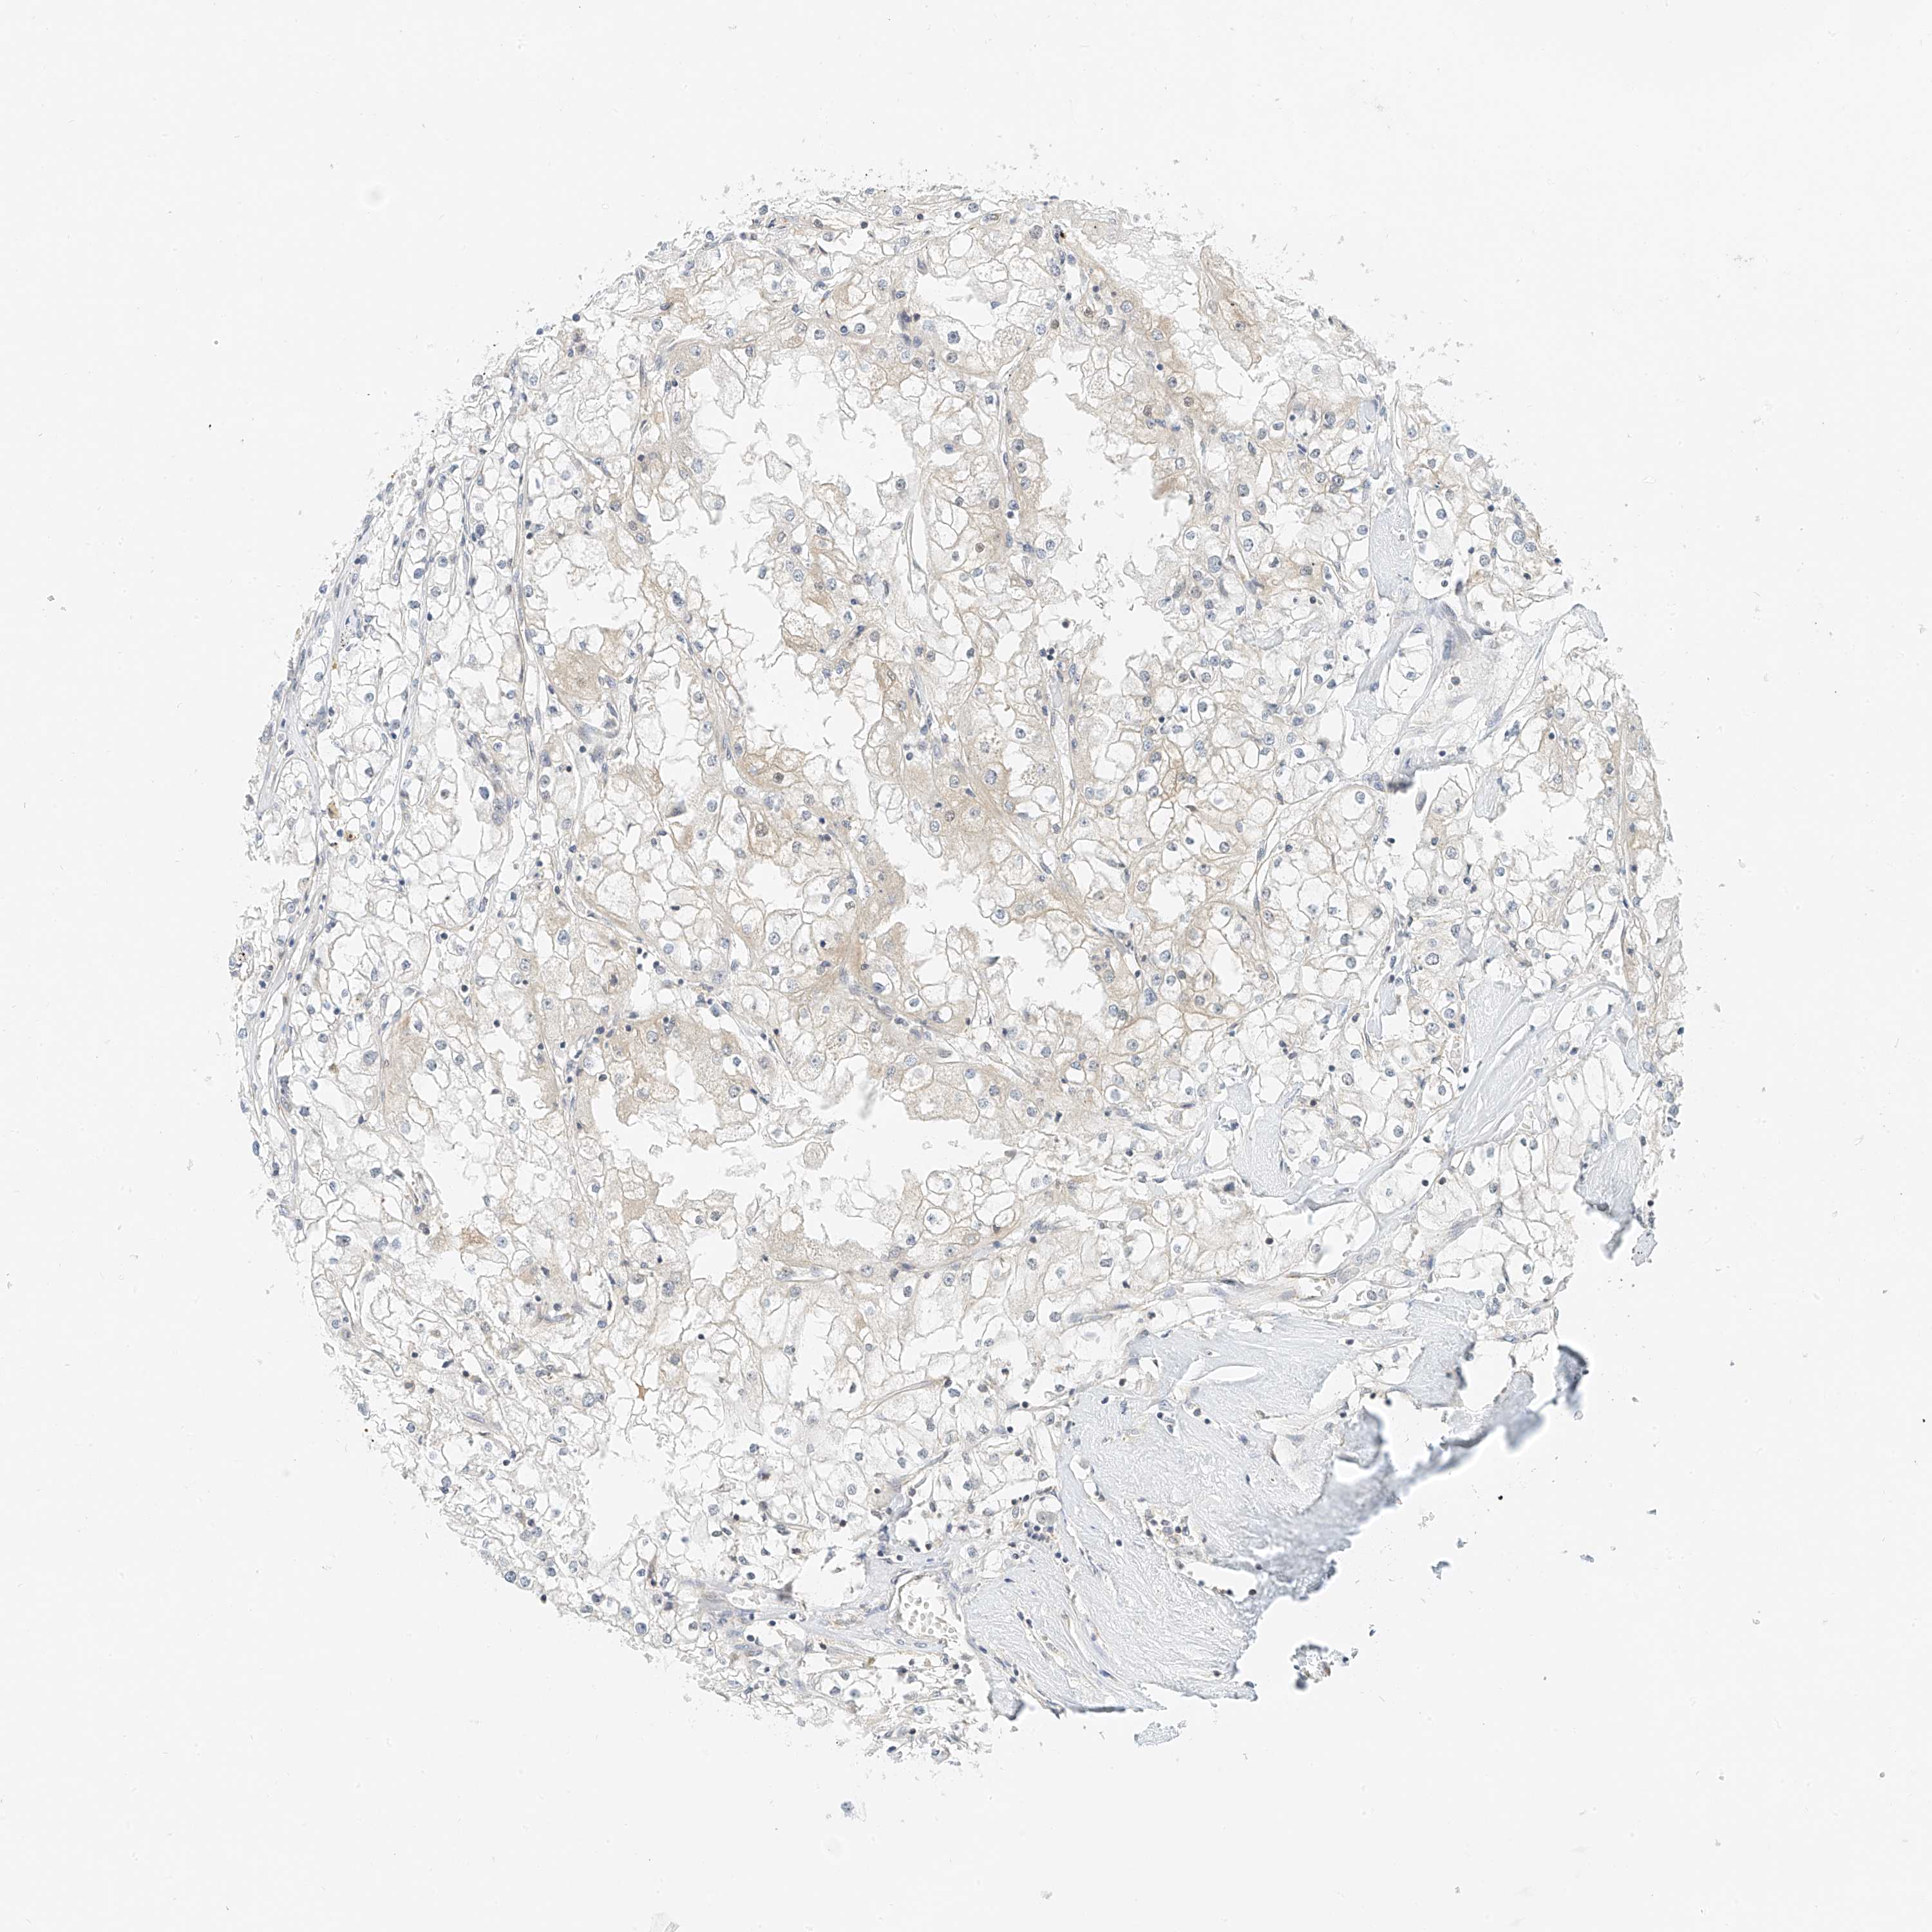

KIDNEY RENAL CLEAR CELL CARCINOMA (VALIDATION) - Interactive survival scatter ploti

The Survival Scatter plot shows the clinical status (i.e. dead or alive) for all individuals in the patient cohort, based on the same data that underlies the corresponding Kaplan-Meier plots. Patients that are alive at last time for follow-up are shown in blue and patients who have died during the study are shown in red.

The x-axis shows the expression levels (FPKM) of the investigated gene in the tumor tissue at the time of diagnosis. The y-axis shows the follow-up time after diagnosis (years). Both axes are complimented with kernel density curves demonstrating the data density over the axes. The top density plot shows the expression levels (FPKM) distribution among dead (red) and alive patients (blue). The right density plot shows the data density of the survived years of dead patients with high and low expression levels respectively, stratified using the cutoff indicated by the vertical dashed line through the Survival Scatter plot. This cutoff is automatically defined based on the FPKM cutoff that minimizes the p-score. The cutoff can be changed by dragging the vertical line or by entering a cutoff value in the square labeled "Current cut-off".

Under the Survival Scatter plot the p-score landscape (black curve; left axis) is shown together with dead median separation (red curve; right axis). Dead median separation is the difference in median mRNA expression between patients who have died with high and low expression, respectively. It is calculated as follows: median FPKM expression of dead patients with high expression - median FPKM expression of dead patients with low expression. This is intended to aid the user in visually exploring custom cutoffs and the associated p-scores and dead median separation.

Individual patient data is displayed and can be filtered by clicking on one or more of the category buttons on the top of the page. Categories describing expression level and patient information include: high, low, alive, dead, female, male and tumor stages. The scale of the x-axis can be toggled between linear and log-scale by clicking on the "x log" button. Mouse-over function shows TCGA ID, patient information and mRNA expression (FPKM) for each patient.

& Survival analysisi

Kaplan-Meier plots summarize results from analysis of correlation between mRNA expression level and patient survival. Patients were divided based on level of expression into one of the two groups "low" (under cut off) or "high" (over cut off). X-axis shows time for survival (years) and y-axis shows the probability of survival, where 1.0 corresponds to 100 percent.

PPA2 is not prognostic in Kidney Renal Clear Cell Carcinoma (validation)

Best expression cut offi

Based on the FPKM value of each gene, patients were classified into two groups and association between prognosis (survival) and gene expression (FPKM) was examined. The best expression cut-off refers the FPKM value that yields maximal difference with regard to survival between the two groups at the lowest log-rank P-value. Best expression cut-off was selected based on survival analysis .

When clicking on this number, the vertical dashed line indicating cut-off, the interactive survival plot, and the Kaplan-Meier curve will be adjusted to show results based on the best expression cut-off.

: 11.14

Median expressioni

Median expression refers to the median FPKM value calculated based on the gene expression (FPKM) data from all patients in this dataset. When clicking on this number, the vertical dashed line indicating cut-off, the interactive survival plot, and the Kaplan-Meier curve will be adjusted to show results based on the median expression.

: N/A

Median follow up timei

Median follow up time refers to the median time (years) after diagnosis with this type of cancer, based on clinical data from all patients in this dataset.

P scorei

Log-rank P value for Kaplan-Meier plot showing results from analysis of correlation between mRNA expression level and patient survival.

N/A

5-year survival highi

5-year survival for patients with higher expression than the expression cutoff.

For melanoma and glioma, 3-year survival is shown.

5-year survival lowi

5-year survival for patients with lower expression than the expression cutoff.

TCGA RNA samplesi

RNA-seq data is reported as average FPKM (number Fragments Per Kilobase of exon per Million reads), generated by the The Cancer Genome Atlas (TCGA) .

Normal distribution across the dataset is visualized with box plots, shown as median and 25th and 75th percentiles. Points are displayed as outliers if they are above or below 1.5 times the interquartile range. FPKM values of the individual samples are presented next to the box plot.

Average pTPM 15.1

Number of samples 100